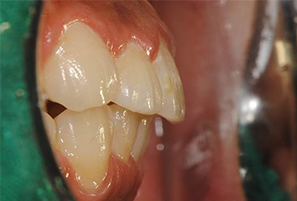

실제 치료 사례

데이몬 교정으로 완성된 아름다운 변화를 확인하세요

돌출 개선 + 얼굴윤곽 변화

자연스러운 치아 이동으로 얼굴형까지 개선